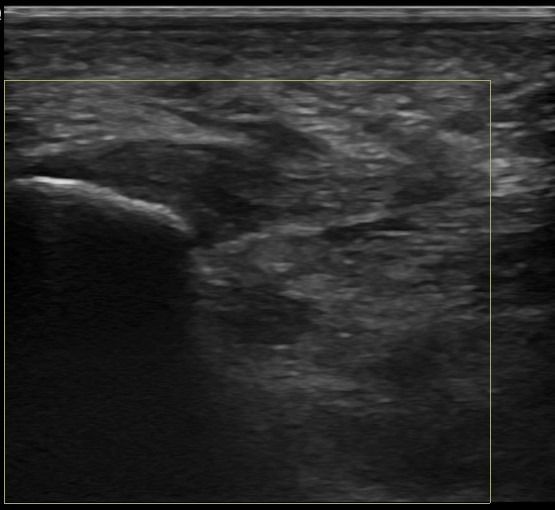

Foot Tendons

Foot Ultrasound allows the diagnosis of tendonitis, tenosynovitis, and rupture in the following tendons:

- Achilles Tendon

- Peroneal Tendons

- Flexor Tendons

- Extensor Tendons